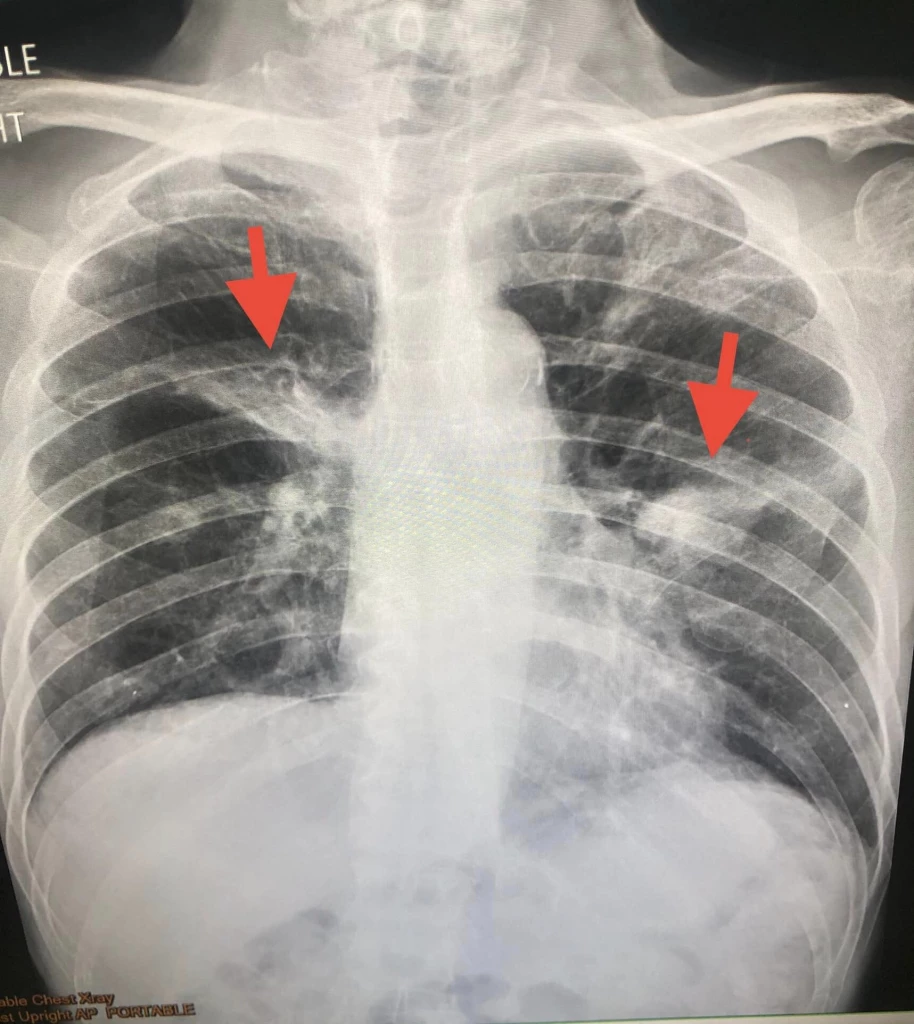

ผู้ป่วยเป็นโรคเส้นประสาทอักเสบแบบระยะเรื้อรัง (Chronic inflammatory demyelinating polyradiculoneuropathy หรือ CIDP หรือโรคซีไอดีพี) ทำให้แขนขาชาและอ่อนแรง 3 เดือน กำลังรักษาด้วยยาสเตียรอยด์ขนาดสูงและยากดภูมิเซลเซ็ป (cellcept) ตรวจร่างกาย มีไข้ อุณหภูมิ 38.1 องศาเซลเซียส ฟังเสียงปอดปกติ เอกซเรย์ปอดผิดปกติทั้ง 2 ข้าง ทำคอมพิวเตอร์สแกนปอด พบโพรงเล็กๆในบริเวณปอดที่มีปื้นสีขาวหลายตำแหน่งในปอดทั้ง 2 ข้าง

ส่องกล้องเข้าไปดูในปอด พบเสมหะสีขาวเล็กน้อย ส่งเสมหะที่ดูดจากหลอดลมไปตรวจ ย้อมพบเชื้อราสาย ไม่พบวัณโรค เพาะเชื้อราขึ้นแอสเปอร์จิลลัส ฟูมิกาทัส (aspergillus fumigatus) และ aspergillus spp อีกตัวหนึ่งไม่ทราบสปีชี่ส์ ส่งน้ำล้างปอดวัดระดับ bronchial aspergillus galactomannan ให้ผลบวก ยืนยันการติดเชื้อรา aspergillus

สรุป : ผู้ป่วยรายนี้มีภูมิคุ้มกันบกพร่องจากกินยาสเตียรอยด์และยากดภูมิ ติดเชื้อรา aspergillus จากการสูดดมหายใจสปอร์ของเชื้อรา aspergillus ที่เจริญงอกอยู่ในเนื้อกระดาษที่ชื้นของหนังสือเก่าๆลอยออกมาในอากาศขณะหนังสือถูกรื้อ เข้าไปในปอด ทำให้เกิดโรคแอสเปอร์จิลโลสิส ปอดติดเชื้อราแอสเปอร์จิลลัสชนิดรุกราน (invasive pulmonary aspergillosis)